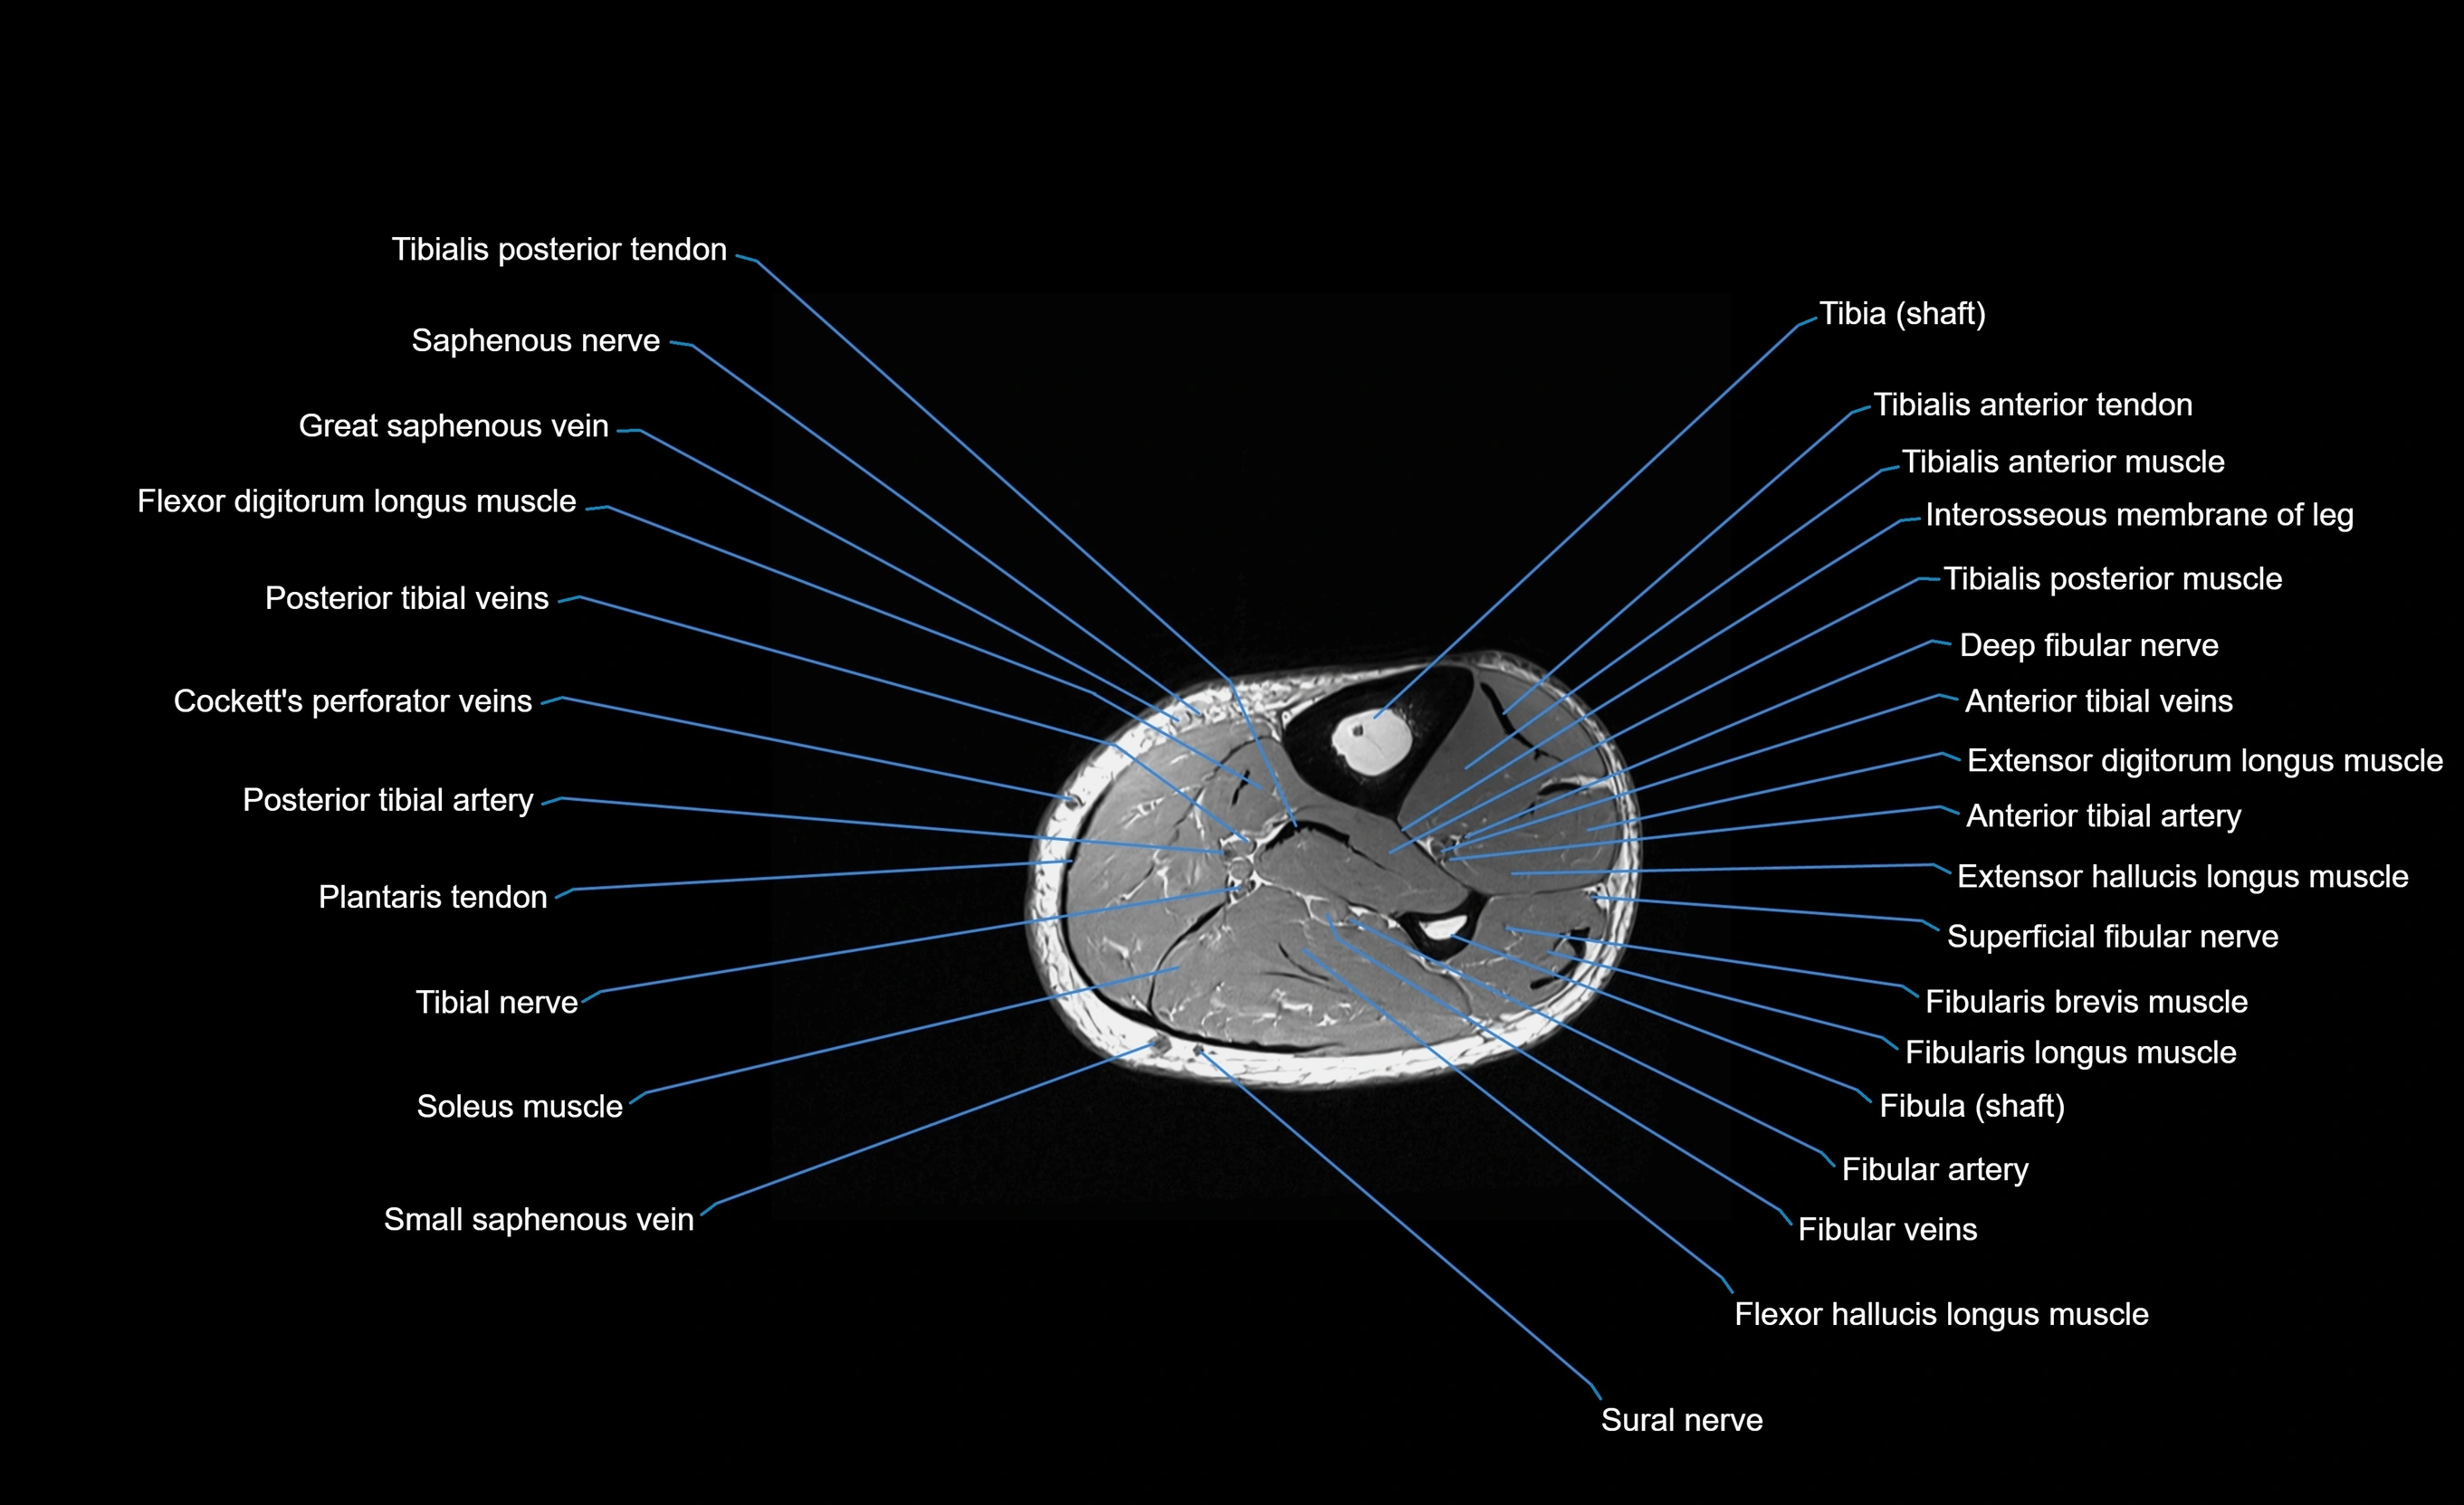

MRI image